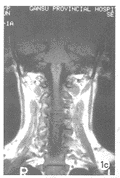

图1 病例1,男,35岁;

图1b MRI知状闰C2I度弱前脱位,椎体前缘不齐。

图1c 1d 冠状位、轴位未见骨折线。